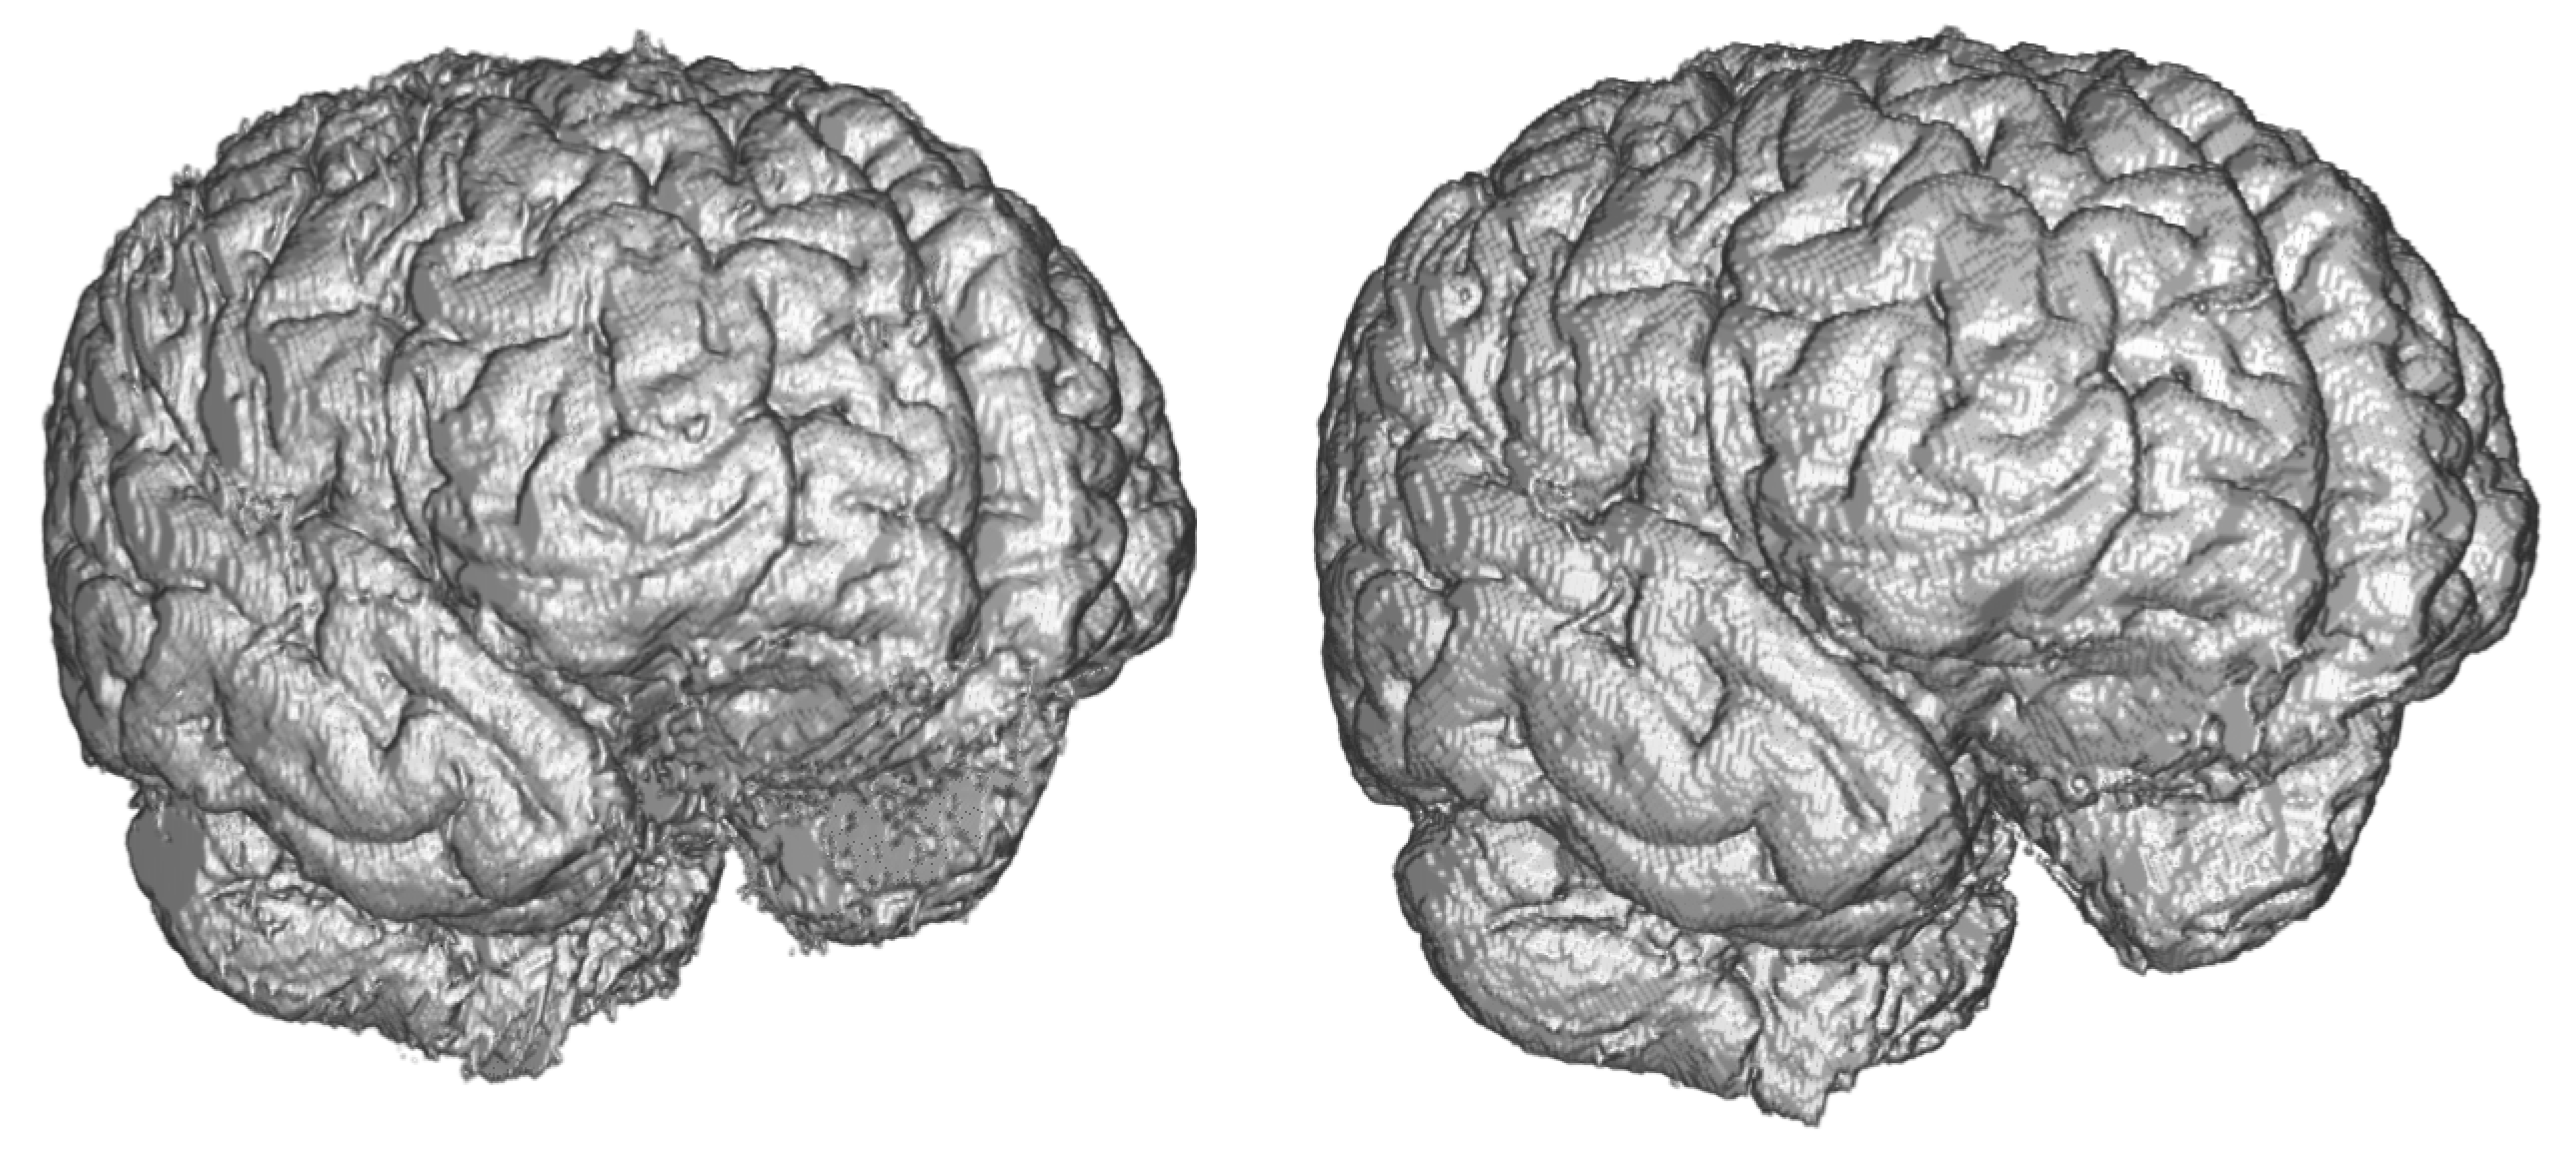

The Dense-U-Net network was trained in the fine-tuning phase (99 epochs) and validated using 3-folds cross-validation. In all five metrics the results are more accurate than a human expert. Output of the segmentation is visualised in Figure 8. It is clearly visible, that the proposed segmentation output overcame the human results and also results of older methods not based on deep neural networks such as the FSL. The network was able to learn the input image features as well as to generalize the brain segmentation problem. All the evaluations were made using data independent to training and the validation data.

Figure 8.

Comparison of ground truth brain model (left) and brain model segmented by Dense-U-Net (right) after the final phase of training.